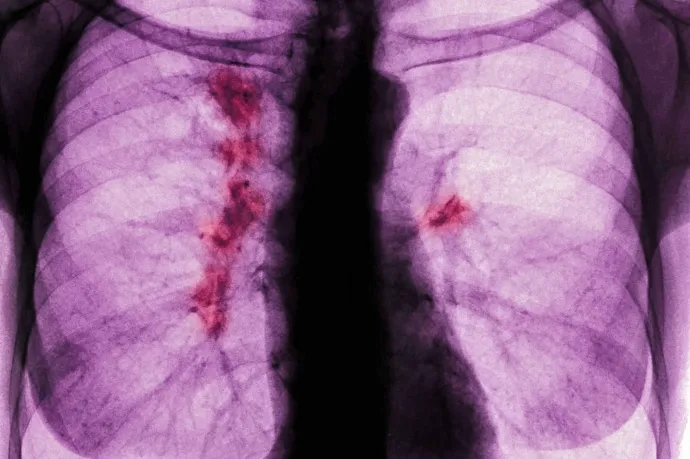

A tüdőrák egy aljas, sunyi betegség, és nincs rá állami szűrőprogramunk sem

Bár a statisztikák szerint javul a halálozási tendencia, egyre több soha nem dohányzó fiatalt is érint a betegség. Ha időben felismerik, az életet menthet.